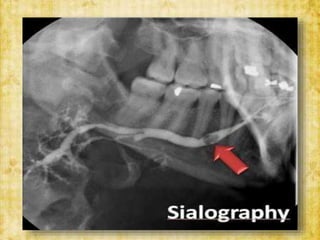

• Sialography : specialized radiographic method

involving filling of ducts and parenchyma with a

radiopaque agent and make them visible on a

radiograph.

INVESTIGATIONS • Radiographs :-AnteroPosterior view - lateral oblique - occlusal view • Sialography : specialized radiographic method involving filling of ducts and parenchyma with a radiopaque agent and make them visible on a radiograph.